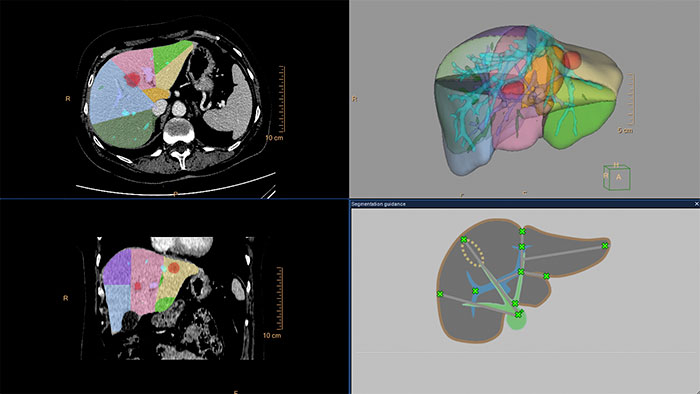

Advanced Liver segmentation

Automatically identifies, segments and quantifies the liver from the portal venous phase of a tri-phase liver scan and classifies the hepatic and portal veins.